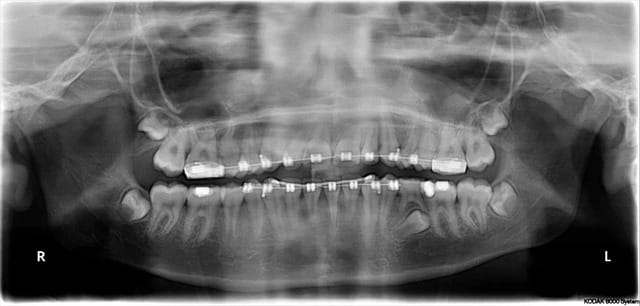

bon, voilà...

patiente de 45 ans, nouvelle pour moi...mais patiente du cab depuis plus de 30 ans (c'est mon père qui l'avait suivie, soins ODF, etc...)

pour raisons professionnelles, elle est partie en Asie pendant près de 10 ans...

par manque de chance, elle s'est explosé la 46 et la 47 (fracture verticale) sur un noyau...extractions, greffe osseuse, implants que j'avais remarqué lors de l'examen intrabuccal du fait du profil d'émergence caractéristique des couronnes

le travail a été réalisé il y a 5 ans, elle ne connaît pas la marque des implants...

pano de contrôle, c'est "propre", j'identifie au premier coup d'oeil la marque mais contrôle en live sur le site whatthisimplant l'image radio pour être sûr à 100%...c'est bien çà c'est du Nobel replace tapered...

je lui dis que je peux assurer le suivi mais pas la garantie du travail qui a été réalisé à Singapour (elle comprend parfaitement...) mais que d'avoir identifié les implants est un plus en cas de bris de céram ou de dévissage ne serait-ce que pour re-commander les pièces...et que bien que je ne pose pas du Nobel, je trouverai le moyen de me procurer les tournevis adéquats pour...

détartrage, et voilà...une patiente ravie d'avoir trouvé un professionnel pour la suivre tout en connaissant mes limites, et visiblement impressionnée elle en a profité pour prendre des RDV pour toute sa famille (mari, gamins pour l'ODF...je ne crois pas que je vais perdre quelque chose...au contraire!!!) je suis sûr que si jamais il y avait un problème, elle ne se poserait même pas la question de savoir vers qui se tourner...et sans me tenir pour responsable de quoi que se soit puisque j'ai été bien clair avec elle depuis le début...

voilà, c'est un petit clin d'oeil, mais çà reflète amha ce qui nous arrivera certainement à tous un jour dans nos cab

vous avez maintenant mon point de vue sur "comment je gère çà", en restant pro, courtois, et simplement en discutant avec les patients comment je jalonne le tout...